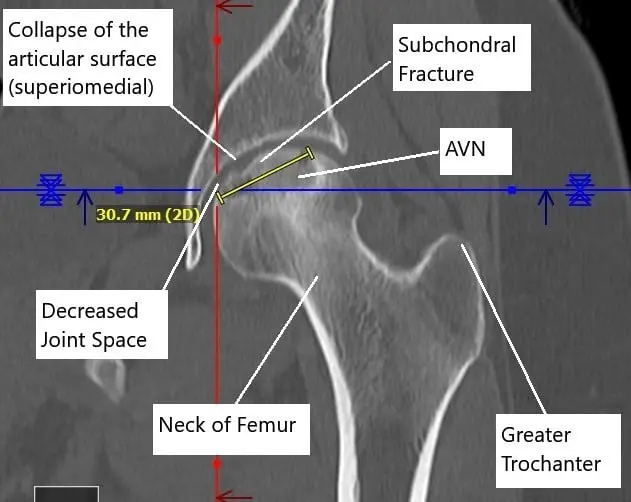

A CT without contrast revealed progression of the avascular necrosis since the core decompression surgery. Avascular necrosis involved the majority of the femoral head, most pronounced superomedially and measuring 3.1 x 3.8 cm.

There was a subchondral fracture superomedially and a mild collapse of the articular surface. There was a mild narrowing of femoral acetabular joint space superomedially with a suggestion of a small joint effusion.

Non-contrast CT image showing AVN changes in the left head of the femur.